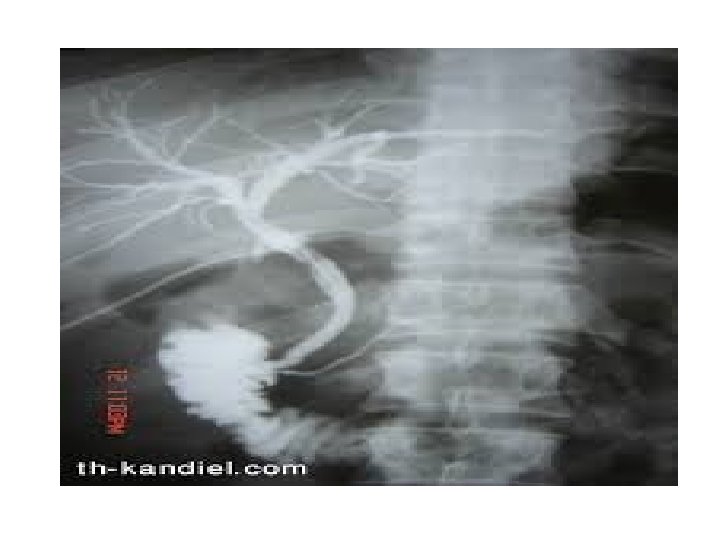

ERCP involves passage of a flexible fiberoptic microscope (endoscope) through the mouth into the small intestine (duodenum). A tube (catheter) is then passed into the common bile duct (and possibly the pancreatic duct), and radiopaque dye is injected. ERCP is the preferred invasive imaging modality because of its relatively low rate of serious morbidity (3% to 5%) and its ability to image and treat diseases of the bile duct, ampulla, pancreas, and duodenum.

Prognosis With cholangiography, the bile ducts are visible on x-ray film. ERCP will show the pancreatic ducts as well. Obstruction within the bile duct system is identified by the lack of radiopaque contrast medium in a segment of the duct. Also, if there is obstruction, the bile ducts usually appear to have a larger diameter (dilated) than normal. Nonobstructed ducts are of normal size.